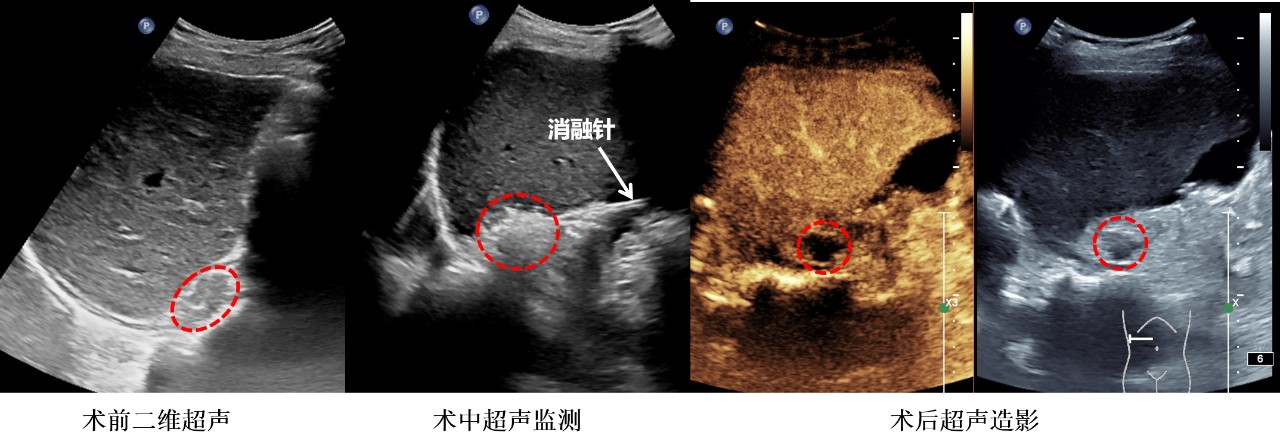

在选择右侧肾上腺内侧分支结节作为治疗靶点后,团队通过超声造影技术在术前明确消融靶点后,实施射频消融术,利用高频电流产生热能消灭病变组织。术后,通过超声造影检查消融范围,确保没有残留病灶。治疗时间仅50分钟,术中和术后均无明显出血。

射频消融术(RFA)作为一种新兴的治疗方式已成功应用于肾上腺肿瘤的治疗中。将CXCR4靶向成像与超声引导的RFA联合,在RFA前可对病灶精准定位,为介入放射科医师制定手术策略提供有力的证据。在RFA过程中,实时超声引导结合对比增强在术中提供了消融区域的可视化,实现了精确的消融边缘并保护了周边组织。术后超声造影,用于评估消融区域,确保病灶已被全面清除,防止可能的残留病变或复发,提高消融的准确性和手术的安全性。